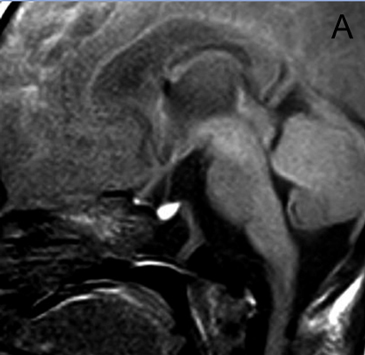

A diferencia de la tomografia computada, que emplea tubos de rayos X, la RM no utiliza radiaciones ionizantes, lo que es una ventaja a considerar en los pacientes pediátricos y en las mujeres embarazadas. La RM tiene una excelente resolución espacial y de tejidos blandos; por ejemplo permite precisar la presencia o ausencia de la neurohipófisis, lo que no es posible con la Tomografia Computada5-7. Con la TAC, con o sin medio de contraste yodado, es posible detectar microadenomas y macroadenomas pituitarios (Figuras 1A y 1B); sin embargo, en los macroadenomas puede ser difícil distinguir las relaciones del tumor con el quiasma óptico, o definir la invasión del seno cavernoso. Además, los artefactos producidos por amalgamas dentales deterioran las imágenes y la dificultad para lograr posiciones cómodas para los pacientes, con el fin de obtener cortes coronales directos, limitan la utilidad de la TAC.

Figura 1A y B. TAC con contraste yodado, corte coronal, muestra un microadenoma lateralizado a izquierda (punta de flecha). Control a los 2 años. TAC con contraste yodado, corte coronal, demuestra aumento de volumen del microadenoma, lo que es infrecuente de observar en clínica (punta de flecha).